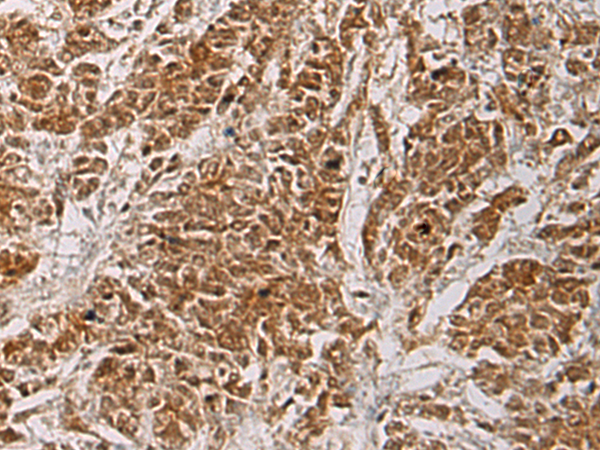

分类: 科研抗体货号: P06710别名: HOX3; HOC3F; HOX3F应用: WB,IHC反应种属: Human, Mouse